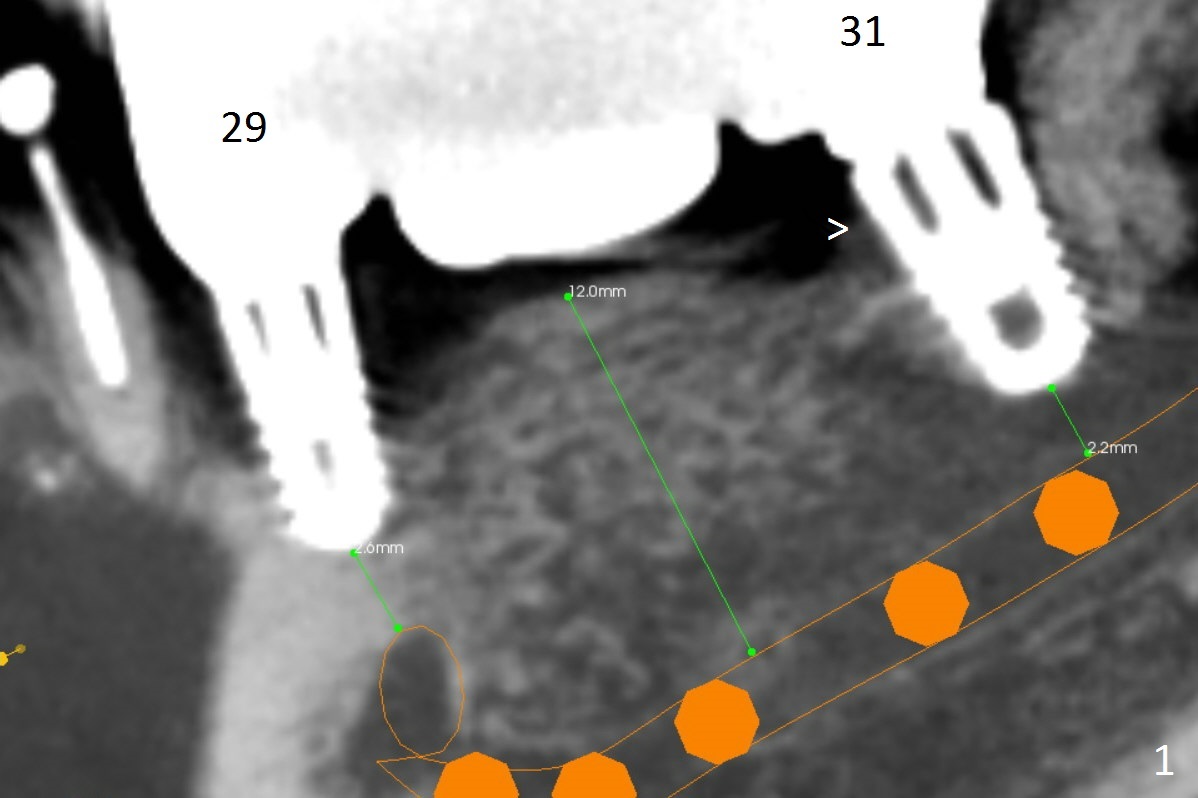

A 64-year-old woman has had sign of periimplantitis at #29 (Fig.1 (CBCT sagittatl section)) in the last 3 years. It appears that the implant is buccally and superficially placed (Fig.3 (coronal section)). Although RCT at #28 is incomplete (Fig.2), there is no symptom or sign of active infection; no treatment will be rendered.

Immediately post implant removal at #29, a 3x10(4) mm 1-piece implant will be placed as lingual as possible (Fig.3). In fact the apical portion of the implant will be lingual to the Mental Loop (Fig.3 orange).

Since the implant at #29 is narrow, an implant at #30 seems necessary (Fig.4). Trim the ridge top for approximately 3 mm until the ridge is about 5.8 mm for a 3.8 mm implant. Control of the depth needs to be precise.

The mesial (Fig.1 >) and lingual (Fig.5 <) threads of the implant at #31 appear to be further bone graft to prevent periimplantitis.